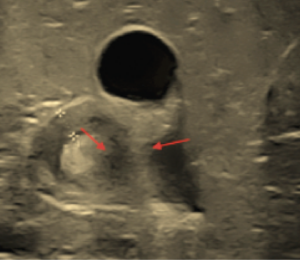

Con la sospecha clínica de estenosis hipertrófica de píloro, se solicita estudio ecosonográfico, el cual se observa en forma clara la imagen característica de la elongación del píloro, con aumento del grosor del componente muscular del píloro. El informe consta de los siguientes datos: -Hígado de ecogenicidad, forma y tamaño normal. -Vesícula biliar de paredes delgadas, sin ecos internos, no existe dilatación de vías biliares. -Riñón derecho de forma normal. -Engrosamiento de la pared muscular a nivel del píloro, que medido en el centro del canal pilórico tiene un espesor de 3.7 mm y una longitud del canal de 17 mm. -Estómago se halla distendido con contenido alimenticio y aire, retraso en el vaciamiento gástrico en el estudio dinámico.

La clínica del padecimiento conforma una tríada distintiva (vómitos postprandiales violentos, ondas peristálticas de lucha y oliva palpable) que permite el diagnóstico en el 90% de casos 1 3. La ecografía abdominal con sensibilidad de 90-99% y especificidad de 97-100%, en manos expertas, confirma el diagnóstico 1 2 3. La imagen ecosonográfica clásica es aumento del grosor de la musculatura (normal 2 mm) y alargamiento del canal pilórico (normal 12 mm) 1 4 5 6. El uso de bario para un estudio de contraste, la endoscopía digestiva alta, son posibilidades para determinados casos 4 6. El laboratorio, en algunos casos, determinará una alcalosis metabólica hipoclorémica hipokalémica, resultado de la pérdida de cloro en los vómitos y aumento de la concentración de bicarbonato; y la consecuente retención de hidrogeniones por el riñón en detrimento del potasio 1 3 7. Es posible el aumento de la bilirrubina indirecta por disminución del paso del estómago al duodeno, con incremento de la circulación enterohepática.